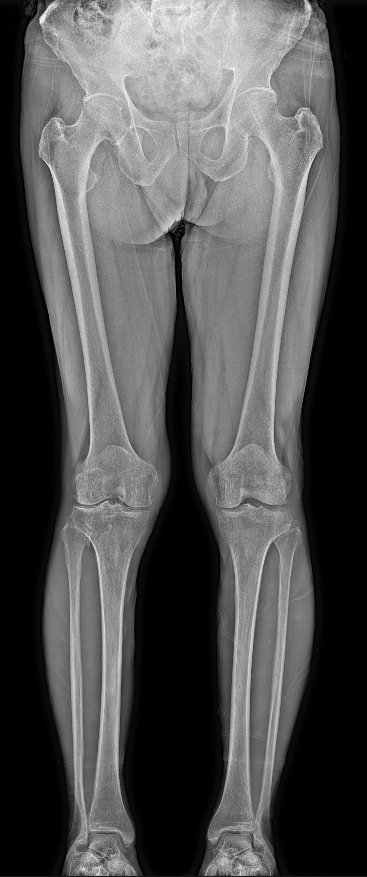

双下肢全长拼接成像:力线平衡的关键判官

应用场景:

膝关节骨关节炎(评估下肢力线、内外翻畸形)、髋膝关节置换术前计划与术后评估、先天性/创伤性下肢畸形(如O型腿、X型腿)、肢体不等长、运动损伤后下肢生物力学评估。

独特价值:

要求患者在自然负重站立位下拍摄,真实反映骨骼在承重状态下的整体力线。精准测量髋-膝-踝角(HKA角)、股骨远端角、胫骨近端角等关键参数,是符合手术指征的病例中,关节外科手术(尤其截骨矫形和关节置换)的重要技术支撑。